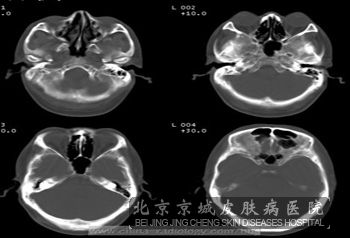

北京京城皮肤医院指出:当患者出现惊厥、皮脂腺瘤、智力低下和内脏改变等典型表现时,可能患者是患有结节硬化症。一般在婴儿期时,如果仅出现反复惊厥,可能也是患有此病的预兆。如果进行CT检查,会发现脑室周围及皮层有密度增高影,这种病变会在早起出现。